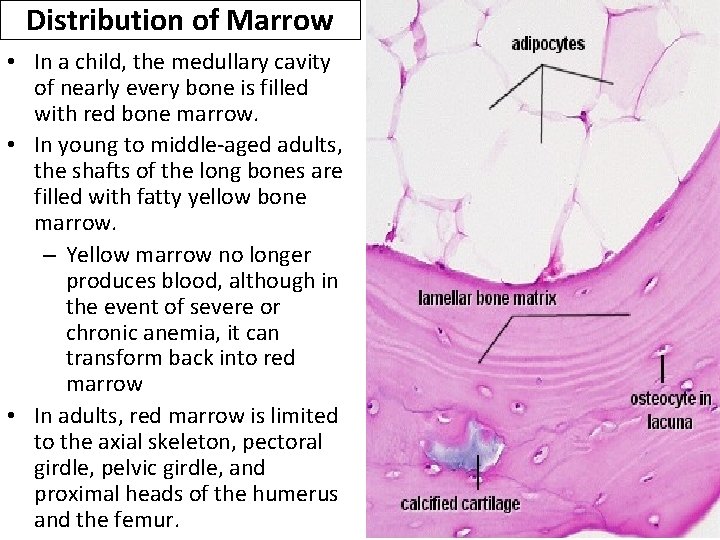

Distribution of Marrow • In a child, the medullary cavity of nearly every bone is filled with red bone marrow. • In young to middle-aged adults, the shafts of the long bones are filled with fatty yellow bone marrow. – Yellow marrow no longer produces blood, although in the event of severe or chronic anemia, it can transform back into red marrow • In adults, red marrow is limited to the axial skeleton, pectoral girdle, pelvic girdle, and proximal heads of the humerus and the femur.